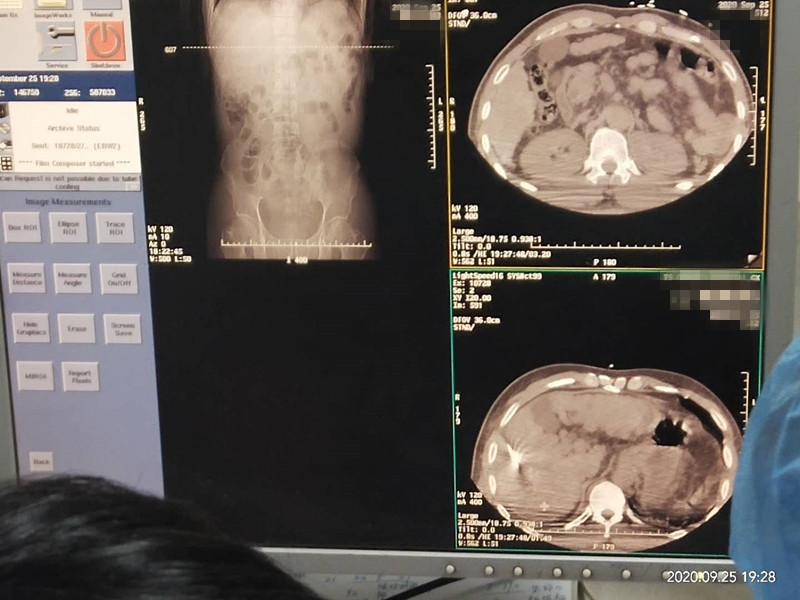

53岁患者肝部氩氦刀冷冻消融

发布人:美国氩氦刀技术官方网站    发布时间:2020/9/29 15:19:10